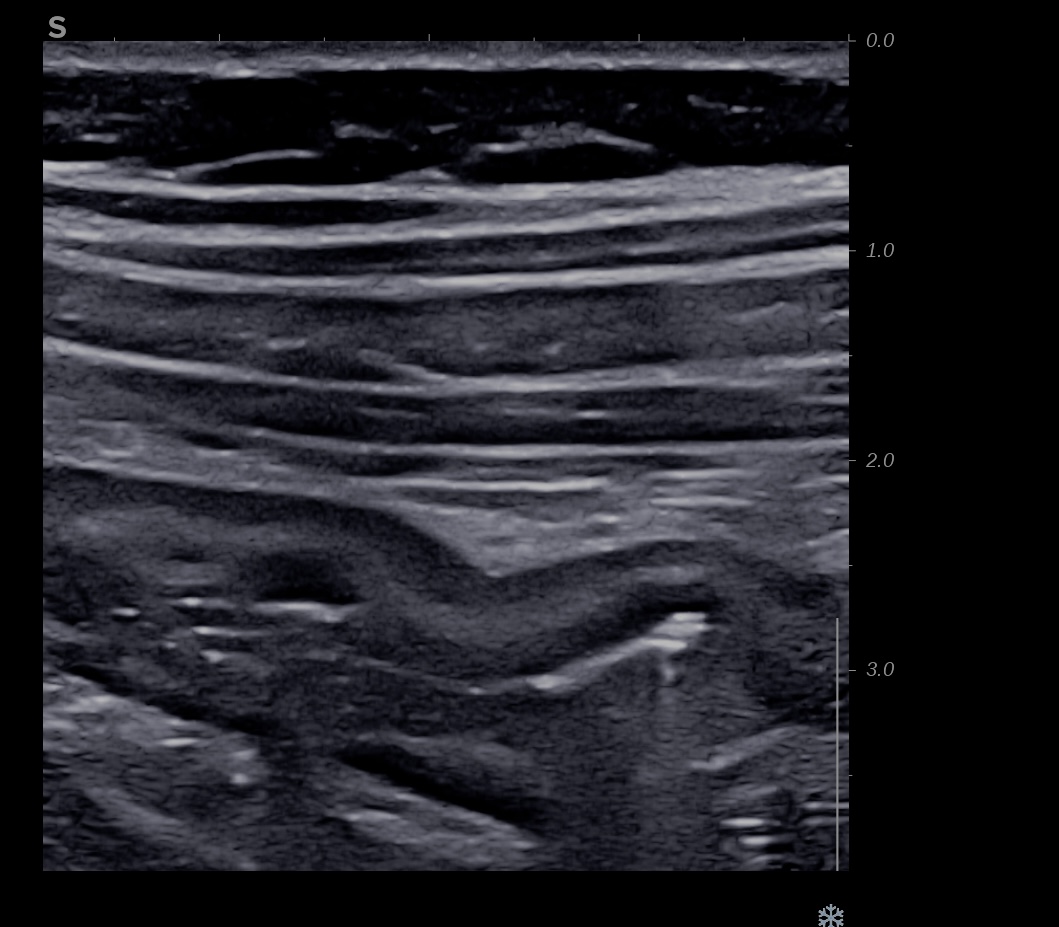

Patiente revue 4 ans plus tard sous vedolizumab Entiyo® en rémission clinique complète, biologie et calprotectine fécale normales, l’échographie (mauvaise échogénicité de la patiente) montre une paroi normalisée entre 1,8 et 2,8 mm d’épaisseur structure en couche conservée.

Le score de Milan MUC est à 3.92 confirmant la rémission échographique